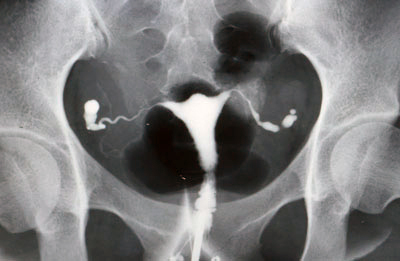

骨盤の傾き

なぜ?この姿勢が「妊娠できにくい姿勢」なのかを説明いたします。

骨盤が後傾して、背中が丸くなることで、足を組みやすくなったり、正座を崩す横座り姿勢になることで、

骨盤が左右に傾き、内臓の圧迫も加わり、子宮、卵巣、卵管が傾き捻じれることで、生殖機能が低下してしまい、更に妊娠できにくくなってしまいます。

あなたも卵管造影された子宮、卵巣、卵管が傾き捻じれていませんでしたか?